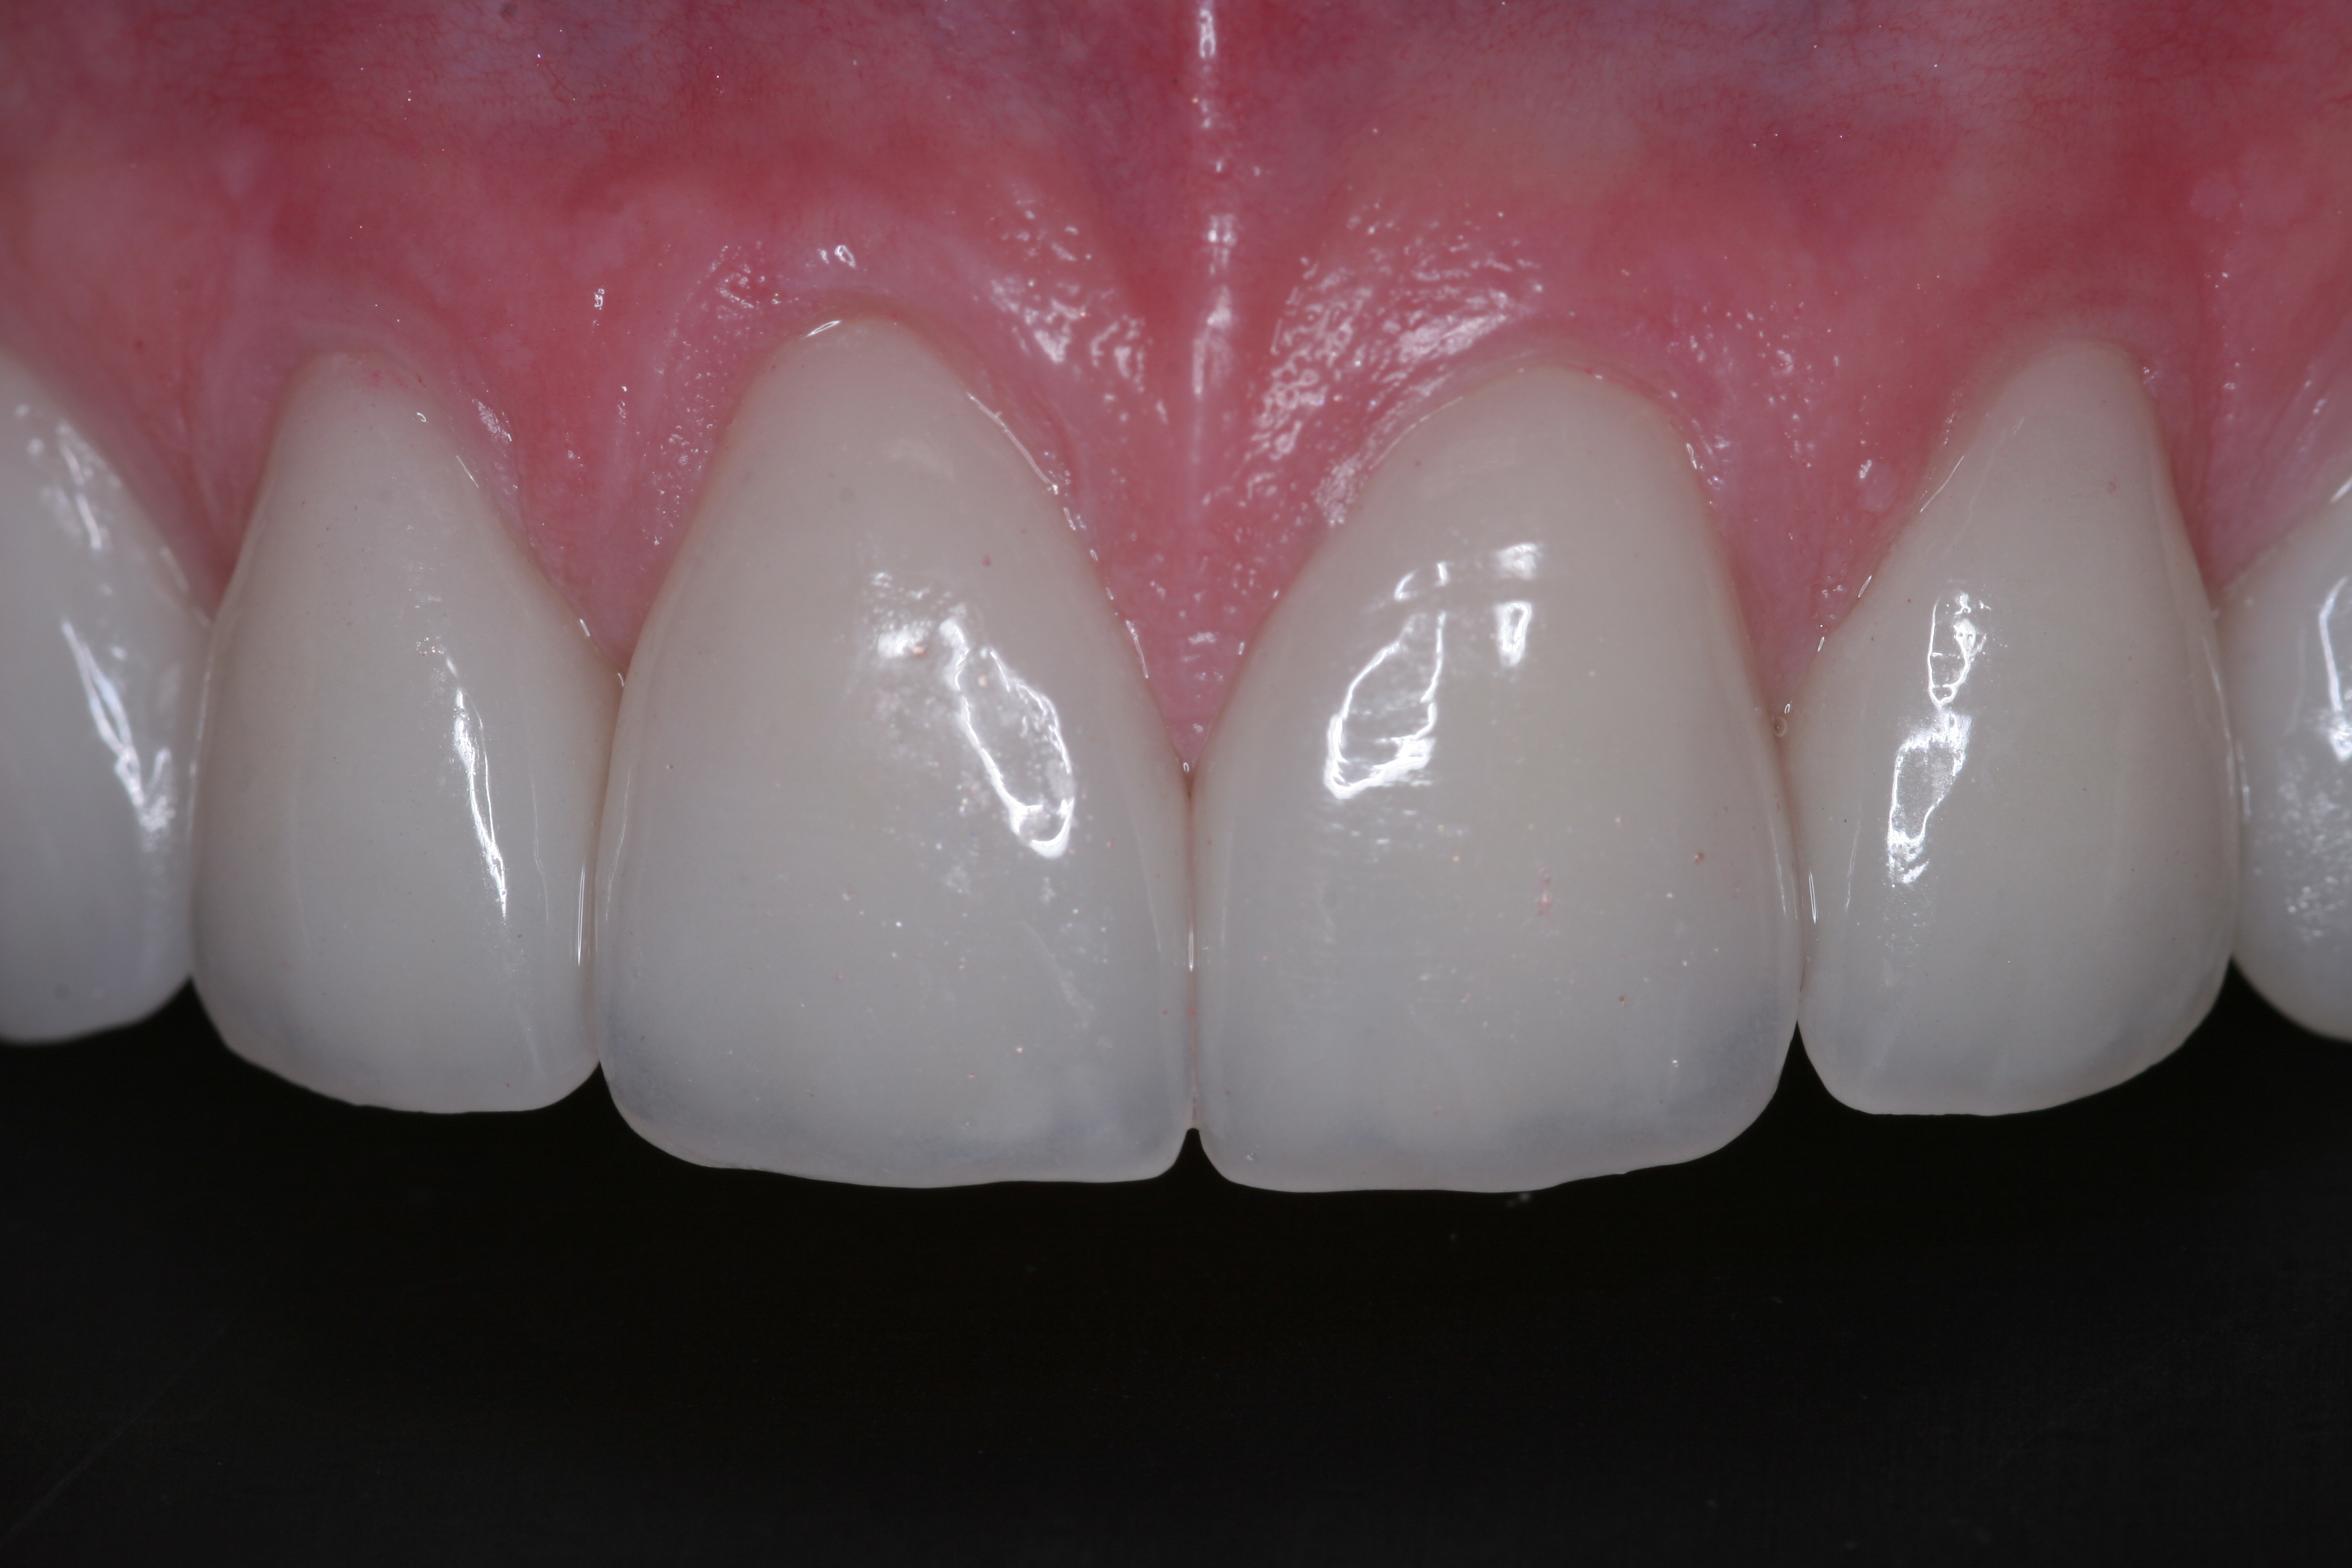

(22.) The final restorations, which reflect the changes modeled through the provisional phase.

Figure 22

Once approved, impressions of the provisionals were taken so the laboratory could precisely copy the 3D position of the anterior teeth as successfully proven in the provisionals. The postoperative result and final functional photographs are shown in Figure 22 through Figure 29. Posterior treatment can now be completed in segments as necessary. Posterior morphology will be developed in harmony with the now corrected anterior contour and functional parameters. The fulfillment of the previously mentioned requirements of occlusal stability were evaluated and refined in the final restorations. The patient was placed in a posttreatment dual-arch B splint appliance to help manage any further parafunctional forces should they occur.